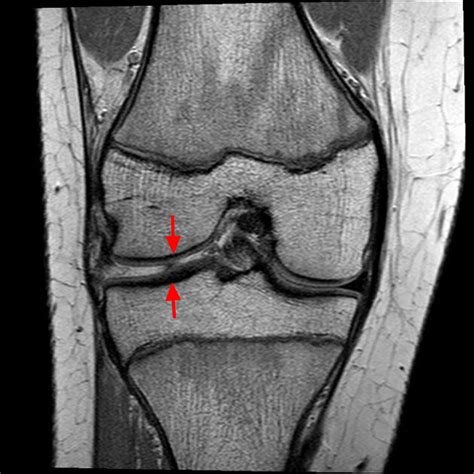

Mri Knee Meniscus How To Read An MRI Of A Radial Meniscus Tear

Understand your health with our expert guide to interpreting Knee MRI images. We break down common scan findings, including meniscus tears, ligament injuries, and cartilage damage. Learn what your radiology report means, how diagnostic imaging aids treatment planning, and what to expect during your orthopedic scan to ensure better recovery outcomes for your joint health.